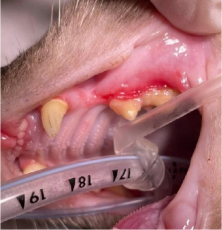

발치전 신경차단술 실시

치조골 삭제